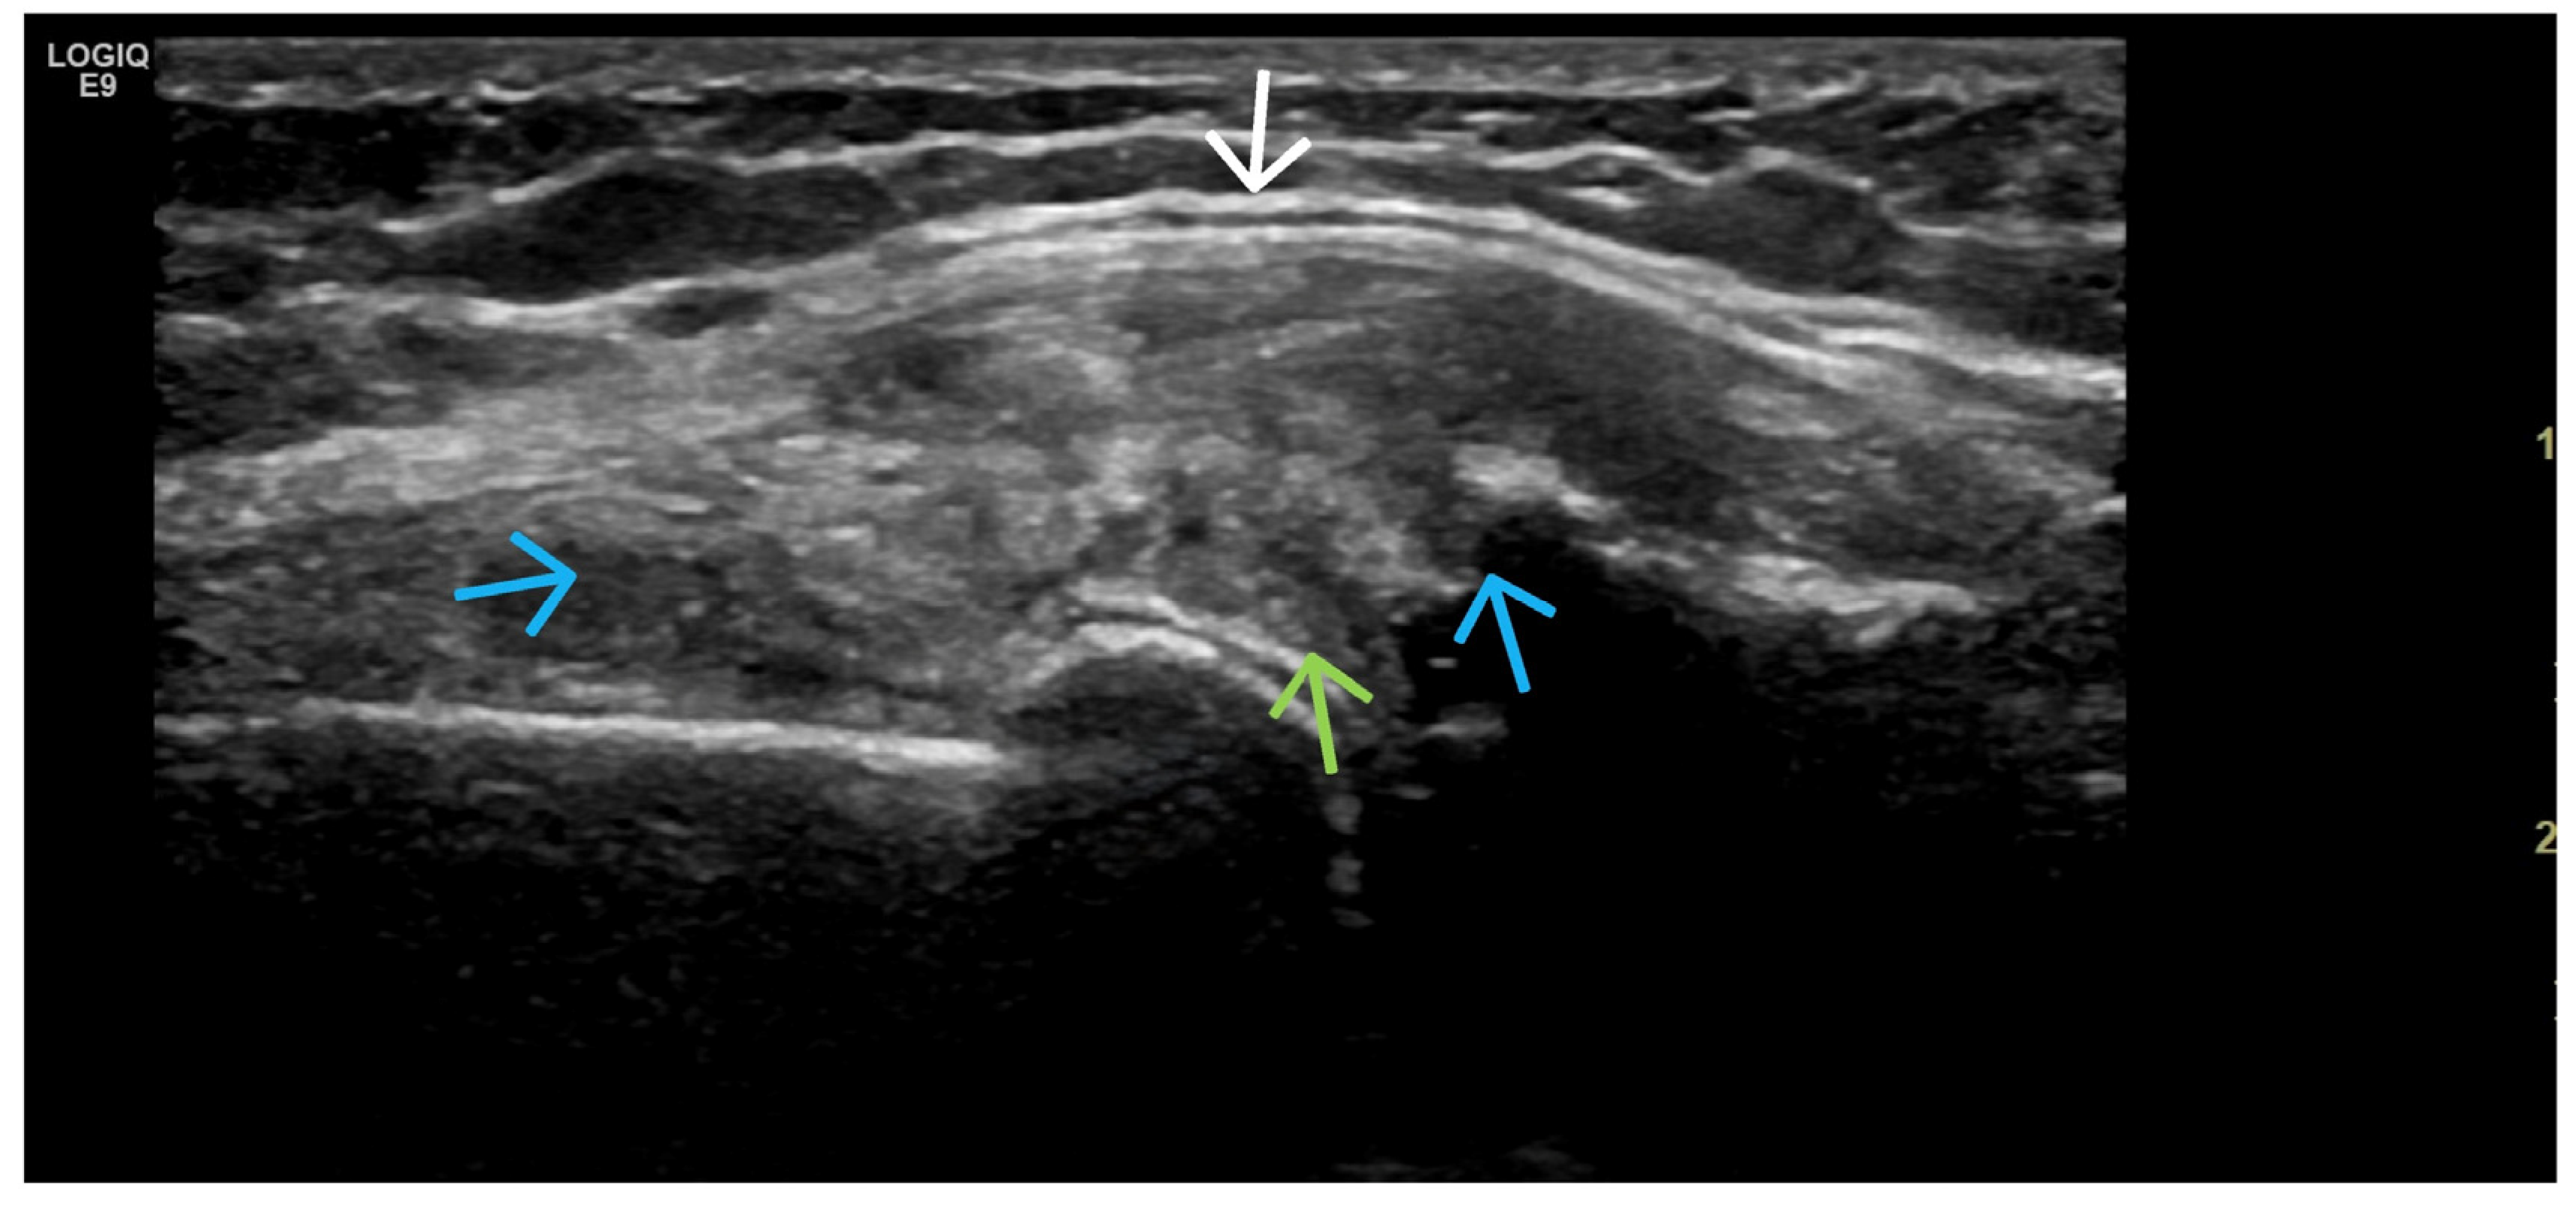

3. Suggestions for US Phenotypes

- Predominant synovial proliferation, fat pads, and Hoffa synovitis (with a small amount of intra-articular effusion);

- Predominant cartilage destruction (with almost no synovitis and intra-articular effusion);

- Altered subchondral bone (superficial bone erosions or osteophytes);

4. Examples of US Phenotypes